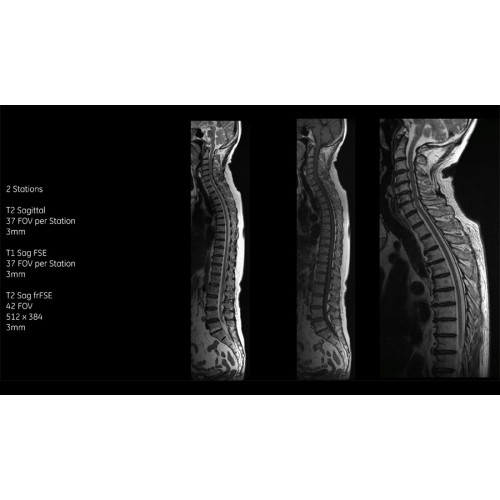

• Технология Digital Surround Technology (DST) — это новая технология объемной оцифровки данных, объединяющая сигналы от каждого элемента катушки. Прекрасное соотношение сигнал/шум и чувствительность поверхностных катушек в сочетании с превосходной однородностью и высокой проникающей способностью встроенной радиочастотной катушки — все это позволяет создавать качественные изображения не только позвоночника, но и всего тела.

Благодаря революционному программному пакету Silent Suite уровень шума снижается до 77 дБ, что всего на 3 дБ выше уровня окружающей среды. Программный пакет Silent Suite теперь включает полный пакет приложений для исследования ЦНС (T1, T2 FLAIR, DWI10, МРА). Кроме того, мы расширили возможности визуализации Silent за пределы ЦНС для исследований скелетно-мышечной системы и позвоночника. Silent Suite – платформа, содержащая в себе все импульсные последовательности для бесшумного сканирования.

Технологии SIGNA Pioneer позволяют проводить полное исследование брюшной полости при свободном дыхании, минимизируя артефакты движения пациента, в том числе с МР-динамическим контрастированием.